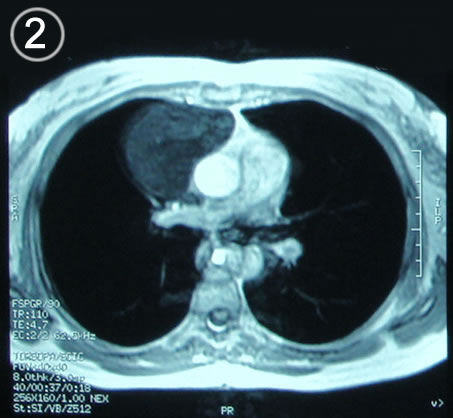

Corte Axial en secuencia T1

Corte mediastino sub aortico nivel cono aortico.

a: lesión redondeada por delante de la aorta y a su derecha la vena pulmonar. contacta con la pared torácica anterior si alterarla.

b: bronquios derecho e izquierdo.  c: la carina traqueal